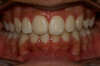

Vues après le Traitement